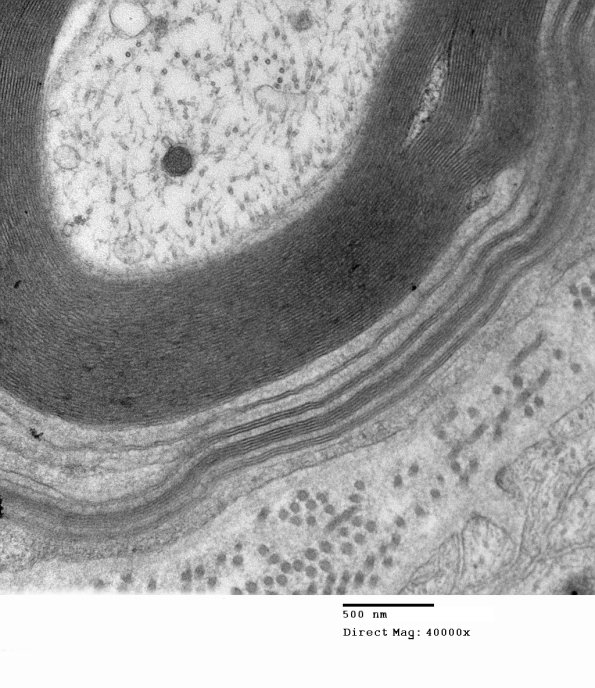

Additional examples of WSM. (electron micrograph)